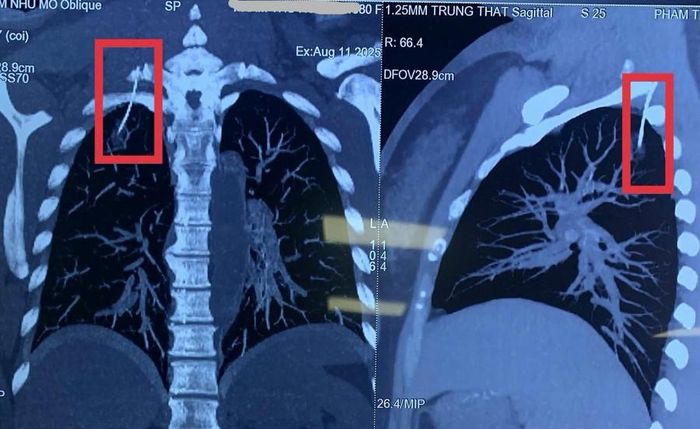

Hình ảnh chụp cắt lớp vi tính dựng hình phát hiện dị vật chọc vào màng phổi phải bệnh nhân. Ảnh: Khoa Ngoại Tổng Hợp 2 - Bệnh viện Thanh Nhàn.

Lo lắng, gia đình đưa bà H. đến bệnh viện để kiểm tra. Hình ảnh chụp cắt lớp vi tính dựng hình phát hiện một dị vật kim loại đã xuyên qua vùng vai, chọc vào khoang màng phổi phải, vị trí ở đỉnh phổi. Các bác sĩ xác định đây chính là kim châm cứu bị gãy hoặc đi lạc trong quá trình thực hiện.